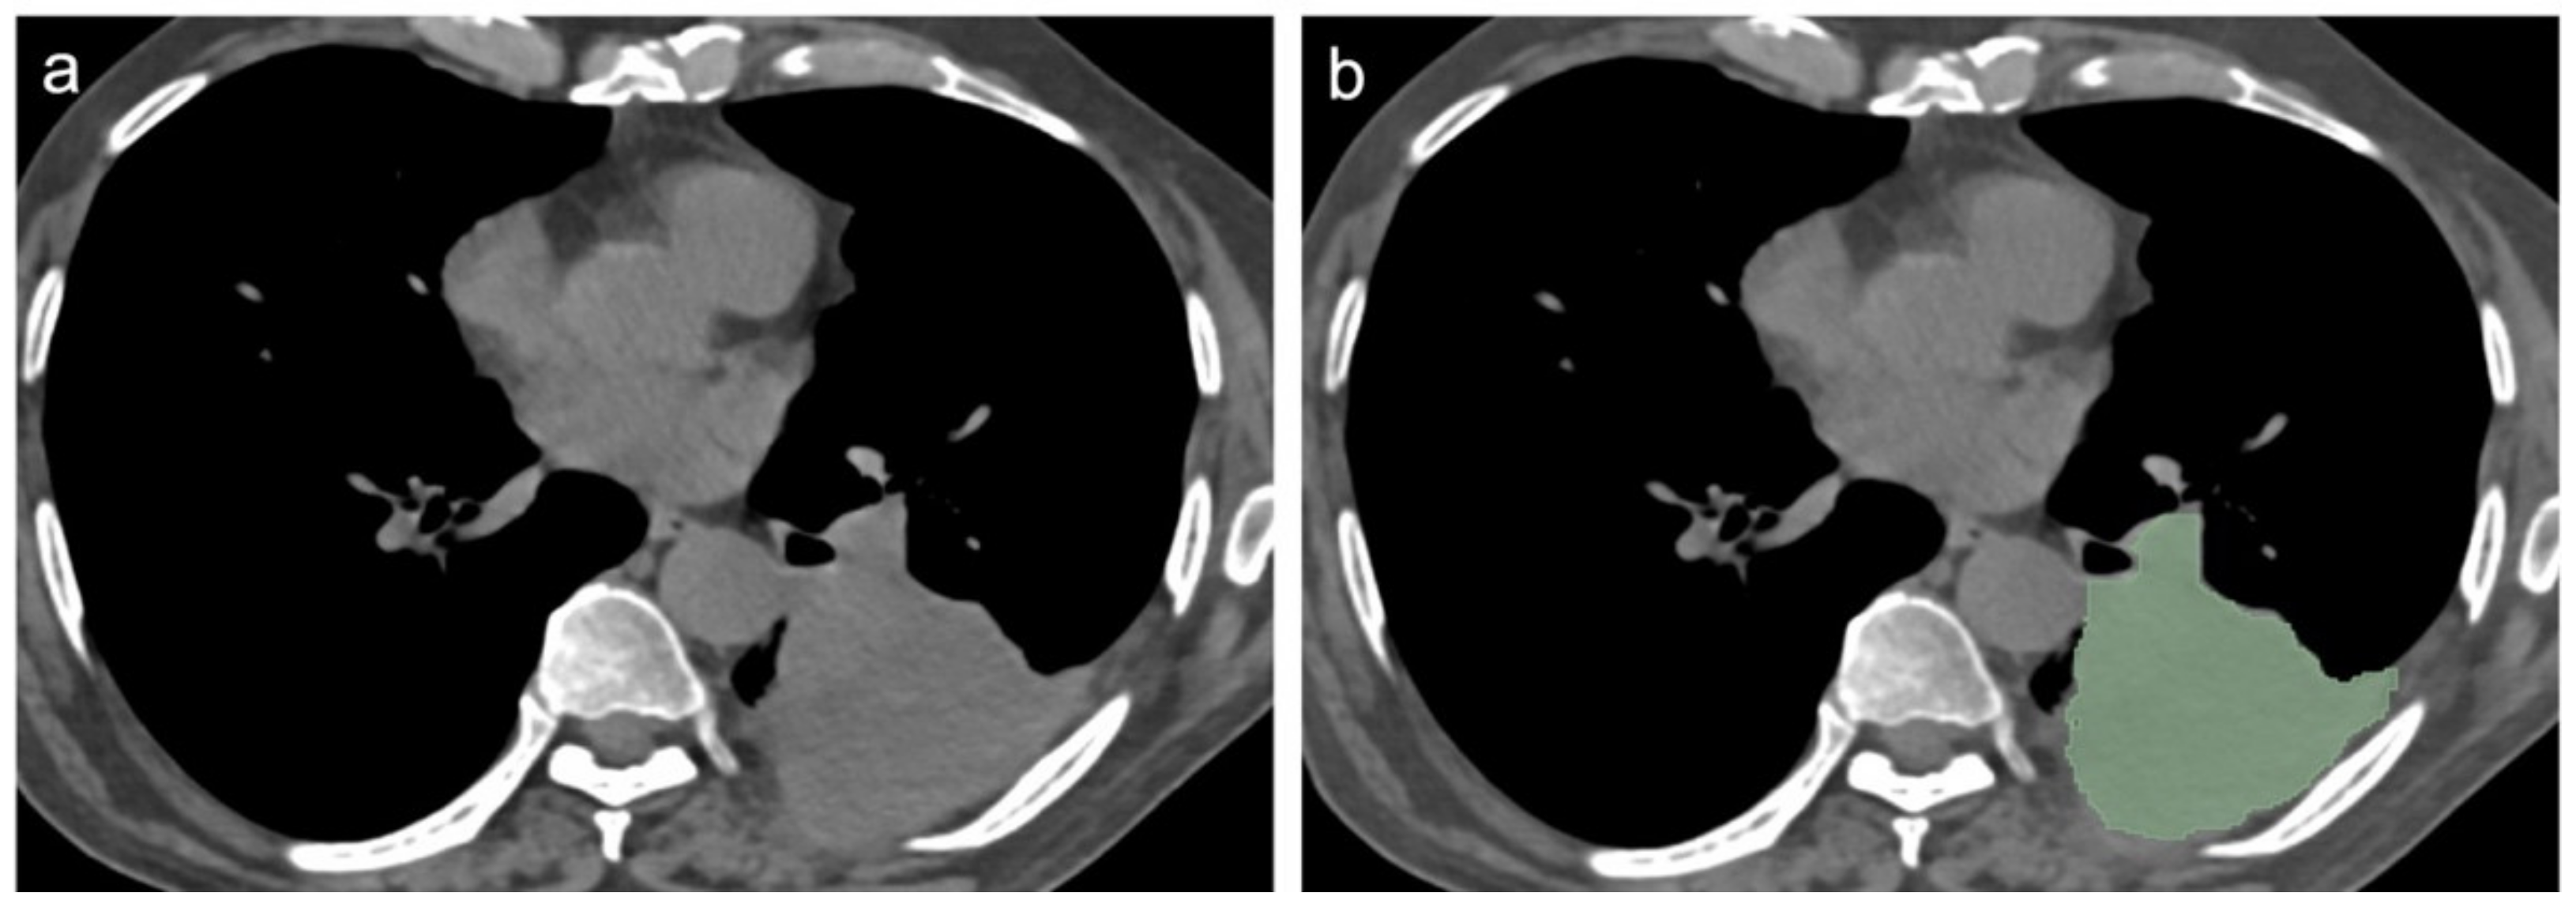

2.3. CT Scans Evaluation and Segmentation Analysis